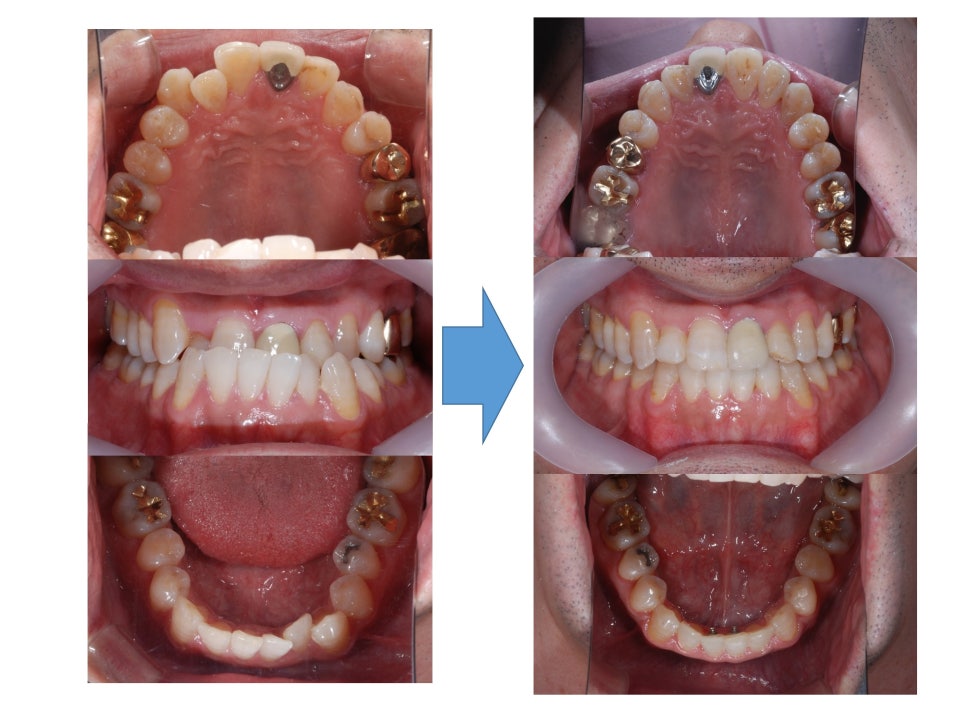

ºñ¼ö¼ú ÁÖ°ÆÅÎ ±³Á¤Ä¡·á ÈÄ ÀÔ´Ï´Ù.

ºñ¼ö¼ú ÁÖ°ÆÅÎ ÀüÈÄ ±³ÇÕÀÔ´Ï´Ù.

¾Æ·¡ÅÎÀÌ ¸¹ÀÌ ¾ÕÀ¸·Î ³ª¿ÍÀÖ¾ú´Âµ¥

¾ç¾Ç¼ö¼úÀÌ ¾Æ´Ï¶ó

±³Á¤Ä¡·á ¸¸À¸·Î

±³ÇÕÀÌ Àß °³¼±µÈ °ÍÀ»

º¼ ¼ö ÀÖ½À´Ï´Ù.

ºñ¼ö¼ú ÁÖ°ÆÅÎ ±³Á¤Ä¡·á ÀüÈÄÀÔ´Ï´Ù.

Á¤»ó±³ÇÕÀ¸·Î

°³¼±ÀÌ Àß µÇ¾ú°í

ºñ¼ö¼ú ÁÖ°ÆÅÎ ±³Á¤Ä¡·á ÈÄ

2³âÀÌ °æ°ú µÇ¾îµµ

ÁÁÀº ±³ÇÕÀ» Àß À¯ÁöÇϰí À־

³Ê¹« ´ÙÇàÀÌ¿´½À´Ï´Ù.

¿À·§µ¿¾È ÁÁÀº ±³ÇÕÀÌ Àß À¯ÁöµÈ´Ù´Â °ÍÀº

ºñ¼ö¼ú ÁÖ°ÆÅÎ ±³Á¤Ä¡·á·Î

°³¼±µÈ ±³ÇÕ¿¡ ¸ÂÃç¼­

¹Ù¸¥ ÀúÀÛ, ¿¬ÇÏ, È£Èí µî

Ä¡¾Æ¸¦ µÑ·¯½Ñ ¿¬Á¶Á÷ÀÇ

¾ÈÂʰú ¹Ù±ùÂÊÀÇ ±ÕÇüÀÌ Àß ÀÌ·ïÁ® Àֱ⠶§¹®¿¡

½Ã°£ÀÌ Áö³ªµµ

±³ÇÕÀÌ Èçµé¸®Áö ¾Ê°í

Àß À¯ÁöµÉ ¼ö ÀÖ´ä´Ï´Ù.

°³¼±ÀÌ µÇ¾ú°í

ÁÁÀº ±³ÇÕÀÌ Àß À¯ÁöµÇ°í ÀÖ½À´Ï´Ù.